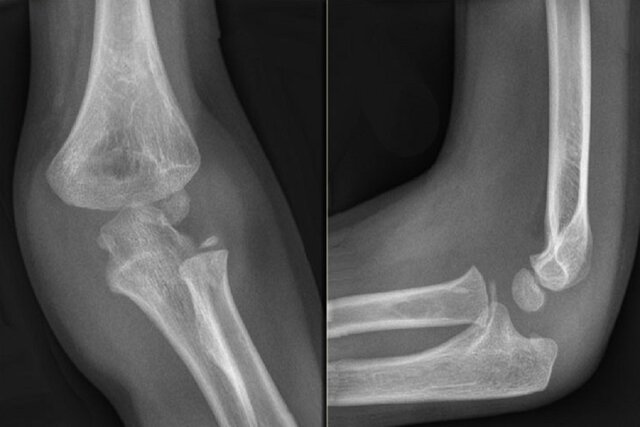

۴۱۵ مورد شکستگی ناشی از پوکی استخوان گزارش شد که ۲۶۰ مورد در زنان و ۱۵۵ مورد در مردان بود. ۳۵۳ مورد شکستگی اندام تحتانی گزارش شد که ۲۱۹ مورد در زنان و ۱۳۴ مورد در مردان بود. ۲۰۳ مورد شکستگی اندام فوقانی نیز گزارش شد که ۱۴۱ مورد در زنان و ۶۲ مورد در مردان بود.

افزایش اندازه دور کمر در زنان، بیشتر با افزایش خطر شکستگی همراه بود. به ازای هر پنج سانتیمتر افزایش در اندازه دور کمر، خطر شکستگی در همه نقاط بدن تا سه درصد و خطر شکستگی اندام تحتانی تا هفت درصد بیشتر بود. به ویژه، ارتباط بین اندازه دور کمر و شکستگی مچ پا قوی بود.

پژوهشگران گفتند: یافتههای ما نشان میدهند که رابطه بین چاقی و شکستگی پیچیده است و میتواند براساس جنسیت متفاوت باشد. در زنان، یک رابطه خطی بین اندازه دور کمر و بروز شکستگی در هر ناحیه از بدن، به ویژه در مچ پا وجود داشت.